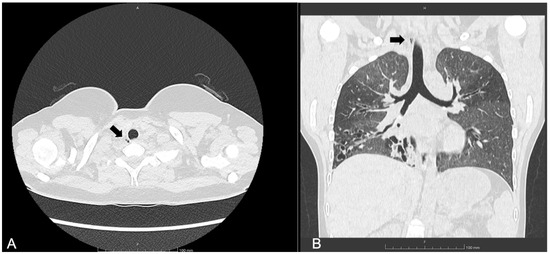

3.1. Patient 1

| 30, M | F508del/ E585X | SA, PA | 73 | 36 | 2, 10 mm, right posterolateral at T2 level | Yes | Visible radiologically and endoscopically | Bronchoscopy after 6 months: stable TD; occurrence of punctiform paracarenal TD |